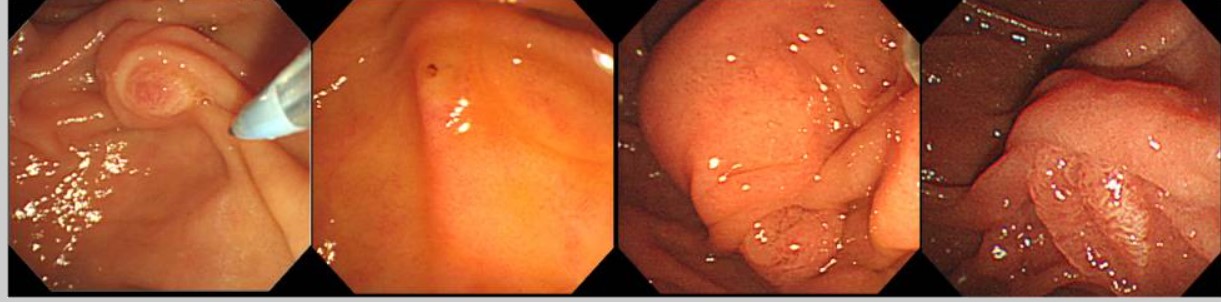

16 yo male attended with worsening RIF pain and guarding.  He reports having asthenia and weight loss over the last month.  He has not had diarrhoea.  His CRP is 110mg/l,  Hb is 10.2mgdl and white cells are 13000.

In view of suspicion of inflammatory process, a CT scan is done after a negative abdomen US for appendicitis.  CT confirms terminal ileitis confined to about 4cm of distal ileum.   Colonoscopy is performed with the attached image in the ileum, being the rest of the colonic mucosa and perianal area normal.

The CDA score is 250 (moderate)

What of the next strategies would NOT be recommended for inducing remission?

crohns TI

Which Kudo pit pattern does this lesion present?